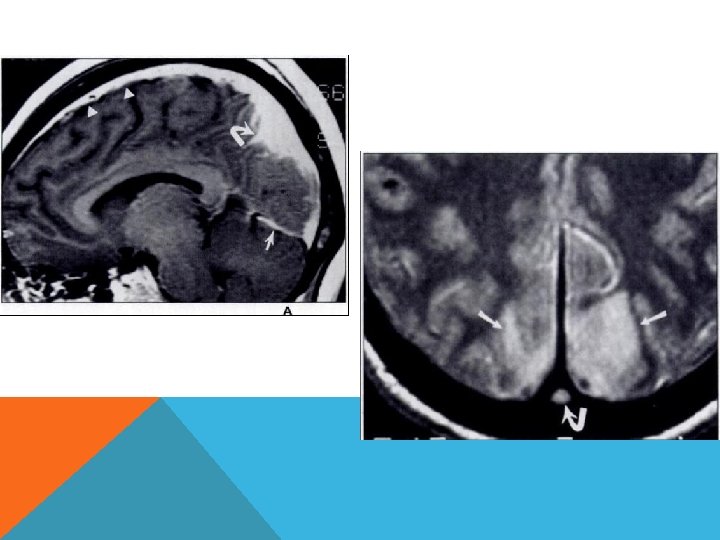

Абсцесс мозга Этиология. Пути проникновения инфекции: 1) путем контактного распространения (при гнойных заболеваниях среднего уха или околоносовых пазух – отиты, мастоидиты); 2) гематогенным путем; 3) через патологическое сообщение между полостью черепа и внешней средой (при проникающей ЧМТ, нейрохирургических манипуляциях, врожденных ликворных свищах).

Патогенез Рост микроорганизмов. Локализованный энцефалит (церебрит) с отеком мозга. Гнойное расплавление очага Формирование капсулы. Клиническая картина Общеинфекционные симптомы (недомогание, лихорадка, тахикардия и т. д. ) Внутричерепная гипертензия Очаговые неврологические симптомы в зависимости от локализации абсцесса (эпилептические припадки, парезы, гемианопсия, афазии, мозжечковая симптоматика)

Диагностика Люмбальную пункцию не проводить! ОАК - лейкоцитоз и ускорение СОЭ. Рентгенография - наличие газа в полости черепа КТ абсцесс выглядит как зона низкой плотности с масс-эффектом. При введении конираста вокруг гиподенсивного центра выявляется тонкая кольцевидная гиперденсивная зона с ровными контурами. МРТ, абсцесс выглядит как относительно гомогенная гиперинтенсивная зона, имеющая слоистую структуру.

Наличие абсцесса является абсолютным показанием к оперативному лечению. Консервативная терапия показана при: обнаружении процесса на стадии энцефалита; небольшие размеры очага (обычно менее 2 см в диаметре); глубокое расположение абсцесса, что создает технические сложности и опасность значительной послеоперационной инвалидизации; наличие множественных абсцессов, которые невозможно дренировать; расположение абсцесса в критических зонах; наличие противопоказаний к оперативному вмешательству.